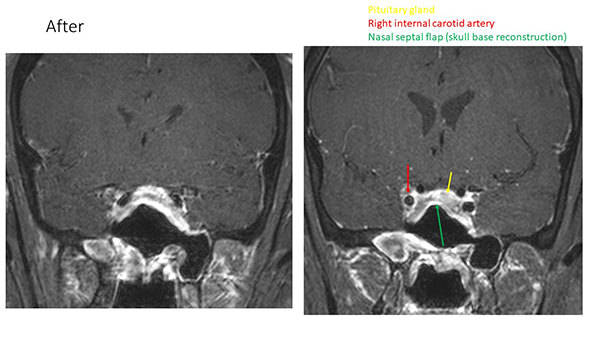

This MRI scan after Pedro's surgery shows the reconstructed nasal septal flap and relieved pressure on the carotid artery.